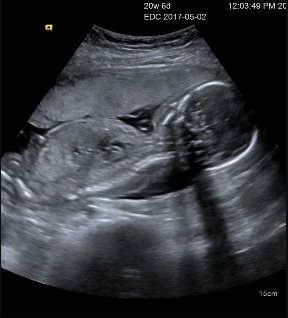

20週6日(20w6d)のエコー写真

20週6日(20w6d・男の子)|咲枝 さん(26歳)

エコー写真撮影時のエピソード:

このエコー写真で初めではっきりと顔を見せてくれました!それまではなんとなくお腹にいるなーっといった感じでしたが、急に愛おしさが増しました。

なんといっても愛する旦那さんにそっくりだったのでかわいくてたまりませんでした!